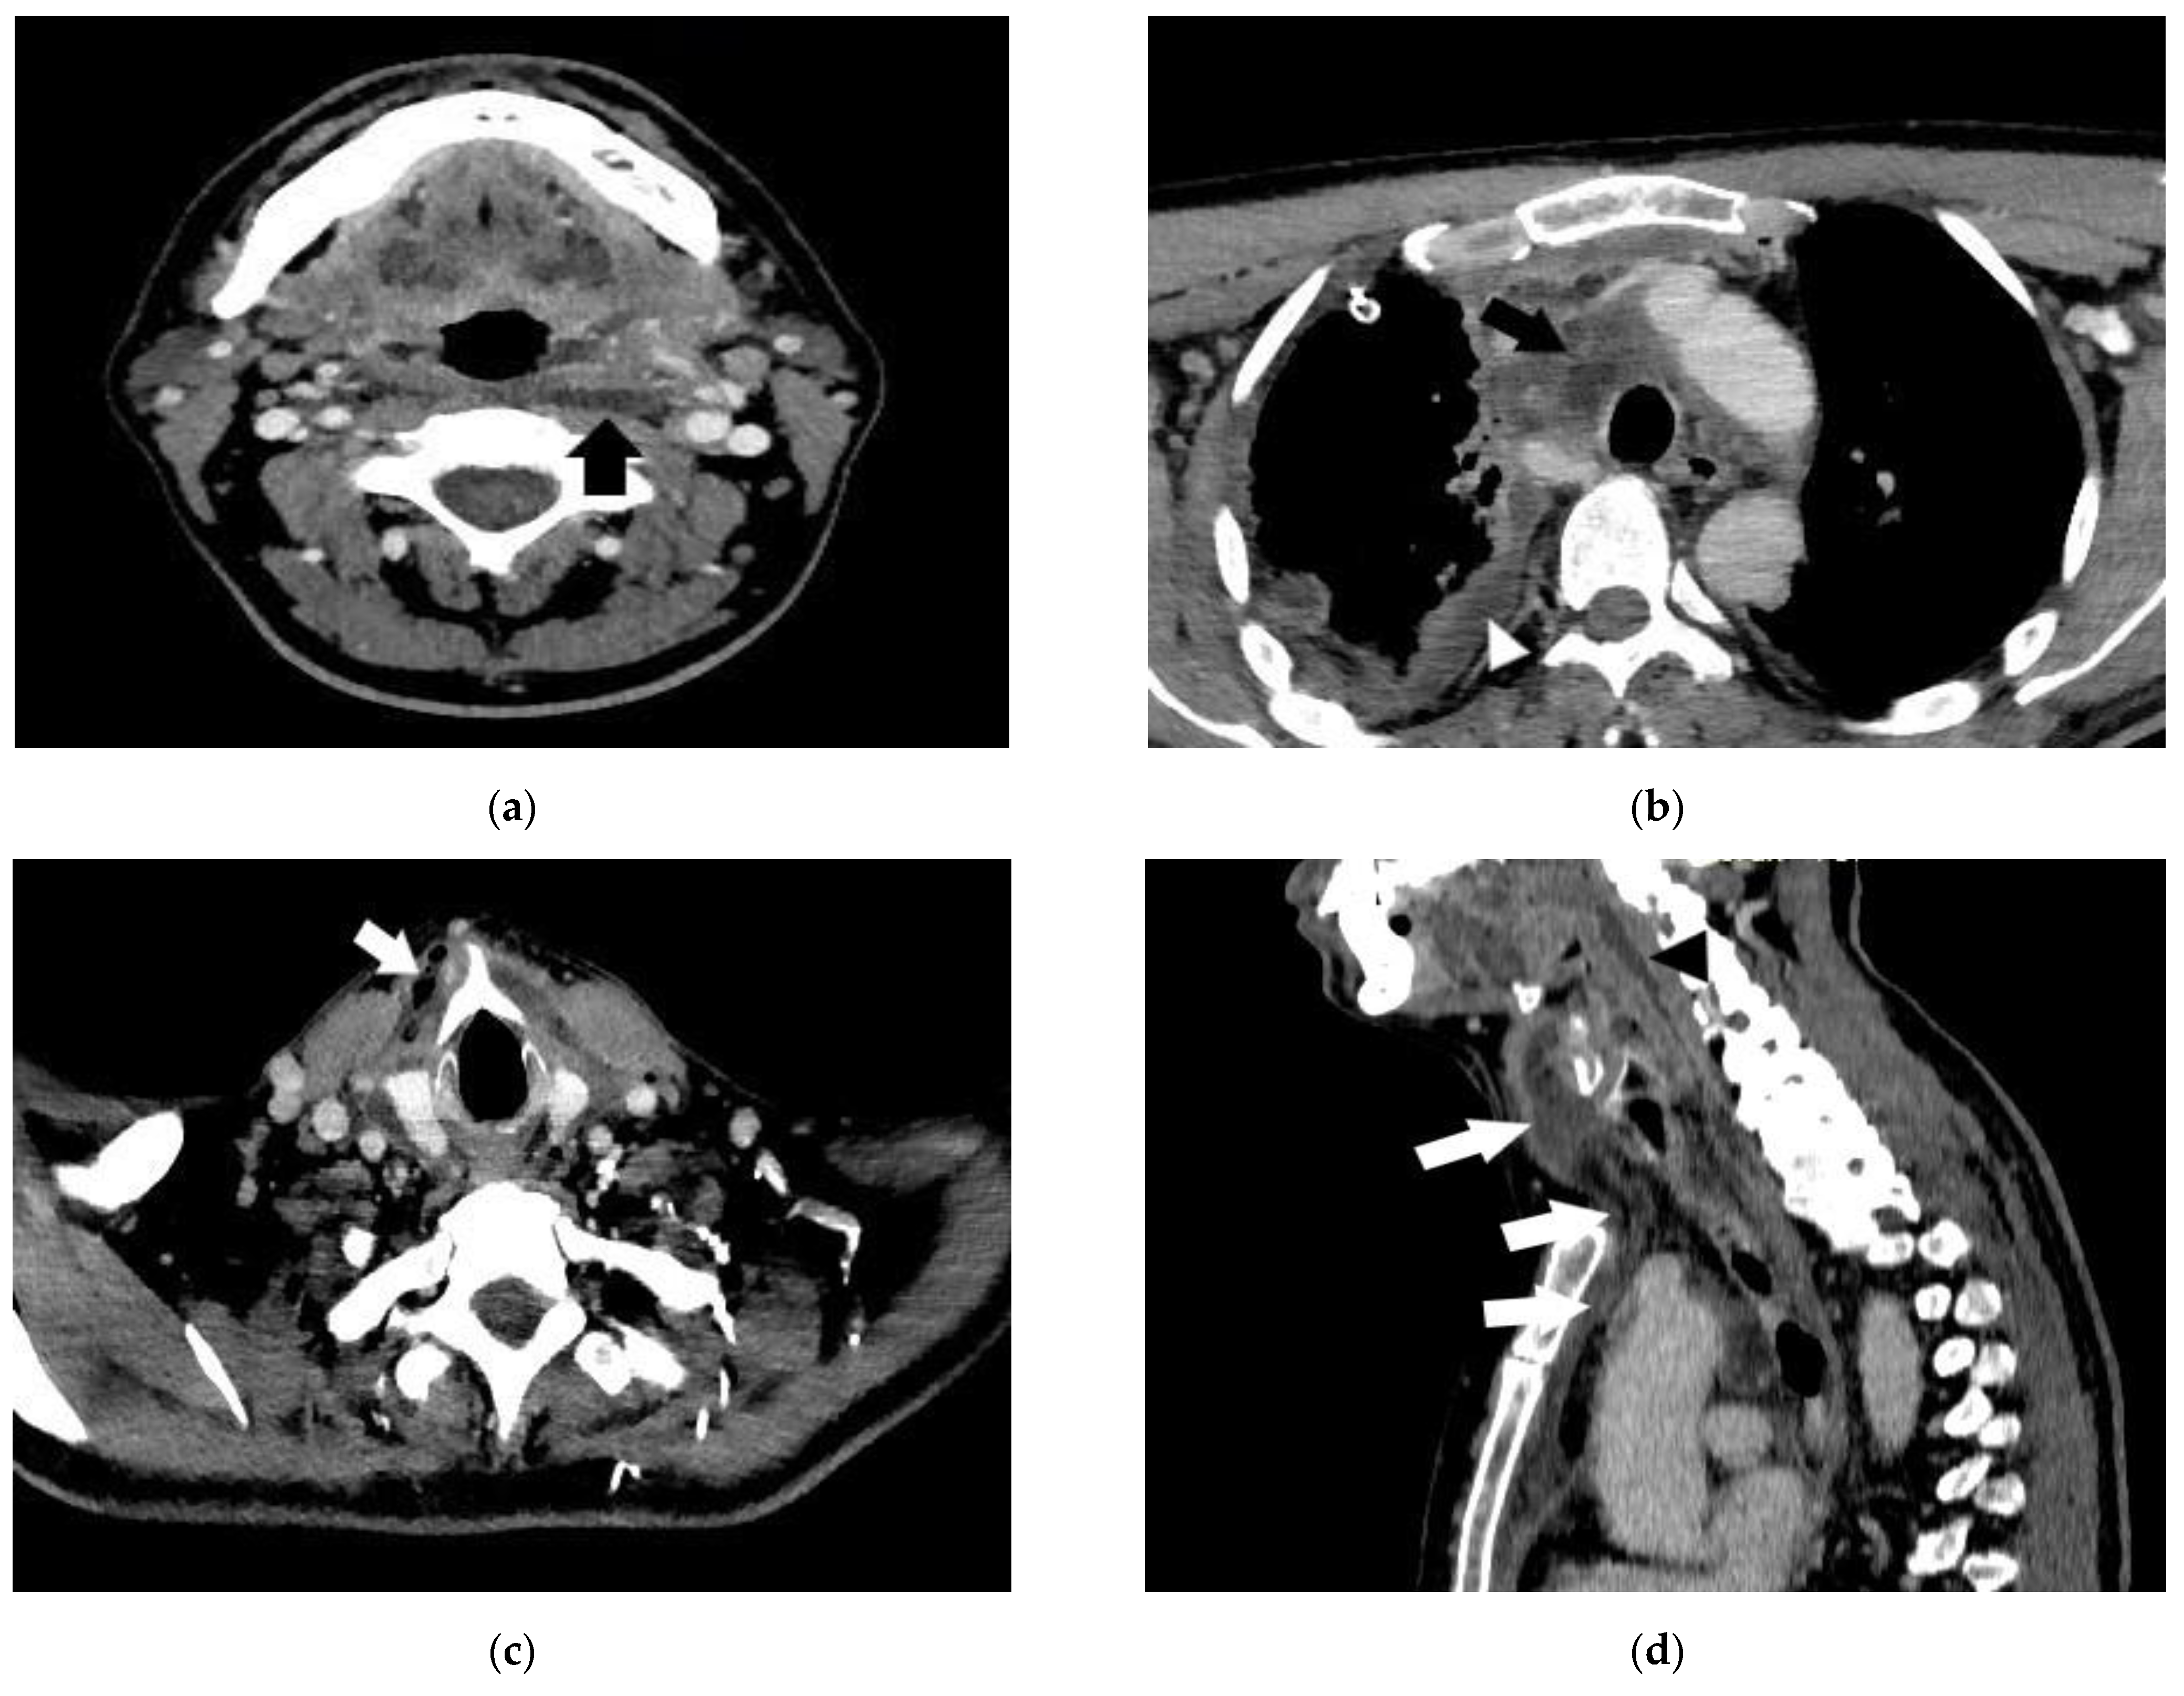

- Case 1.